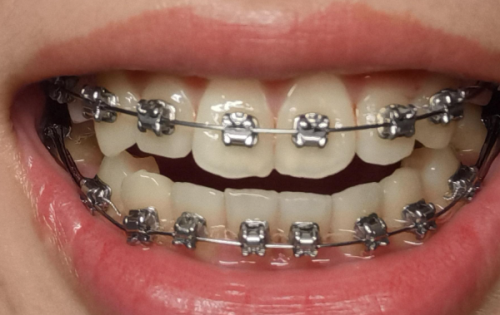

在益阳地区,种植牙需求日益增长,众多市民都在关注哪家医院的种植牙技术好、价格实惠。2025年全新的益阳种植牙医院排名为大家提供了重要的参考依据。了解这些排名不仅能帮助市民选择更靠谱的医院,还能在确保种植牙成效的同时节省费用。接下来,我们就详细介绍一下益阳种植牙医院排名相关的情况。

经过多方面的综合评估,2025年益阳种植牙医院排名中,益阳伢贝健口腔、益阳华雅口腔、益阳德益口腔等名列前茅。这些医院在技术、设备、医生团队以及价格等方面都有各自的优势。下面我们来具体了解一下这些医院的情况。